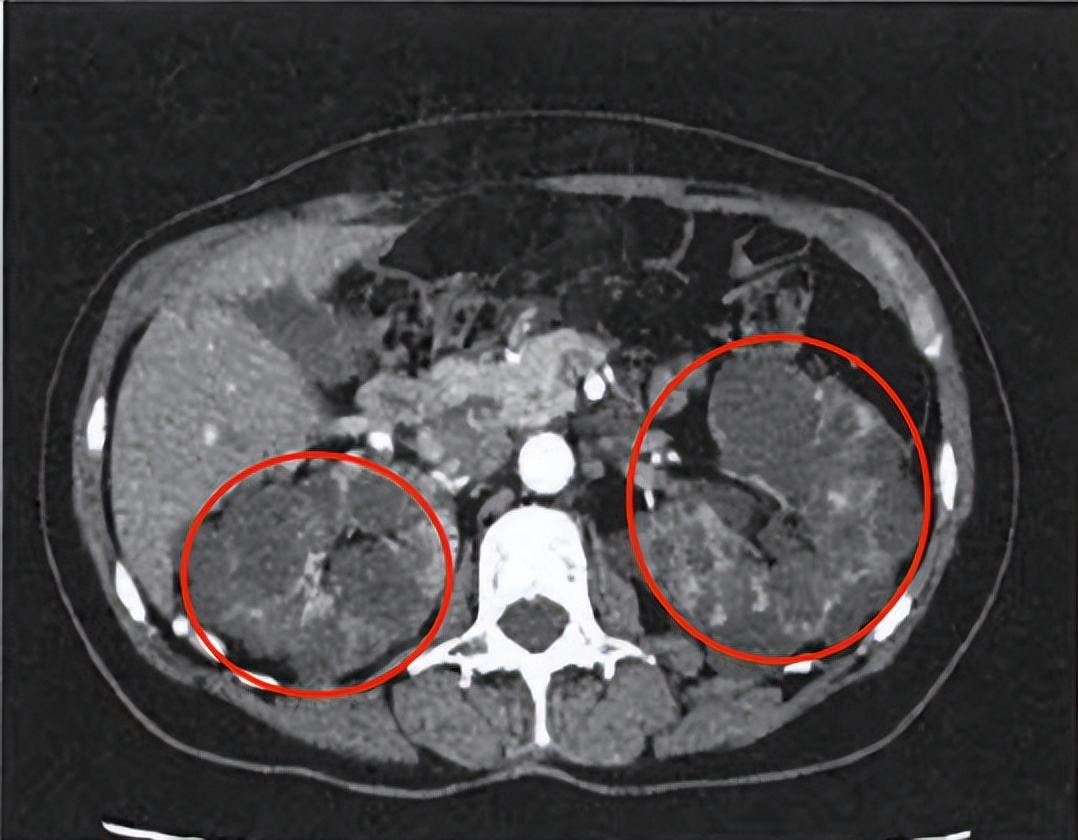

CT显示下的多囊肾☝